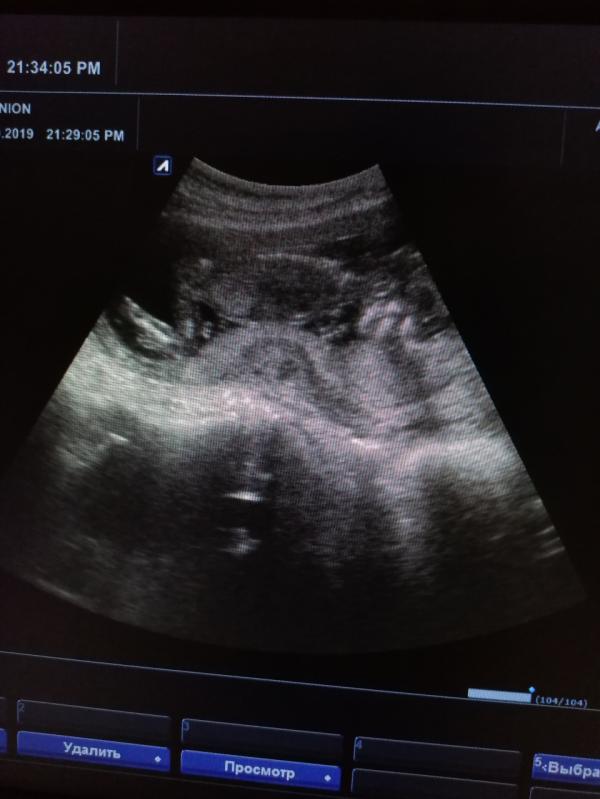

Сегодня была на УЗИ. У меня плацента низковата, по задней стенке. Врач сказала, поднимется. А он уже выгибается и я чувствую это. И тазовые кости расходиться начали. Хожу и слышу как хрустит 🤦♀️